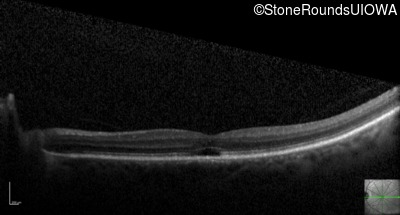

Optical Coherence Tomography - Left - 20/125 -1 sc

Exemplar / OCT Stack

OCT Stack